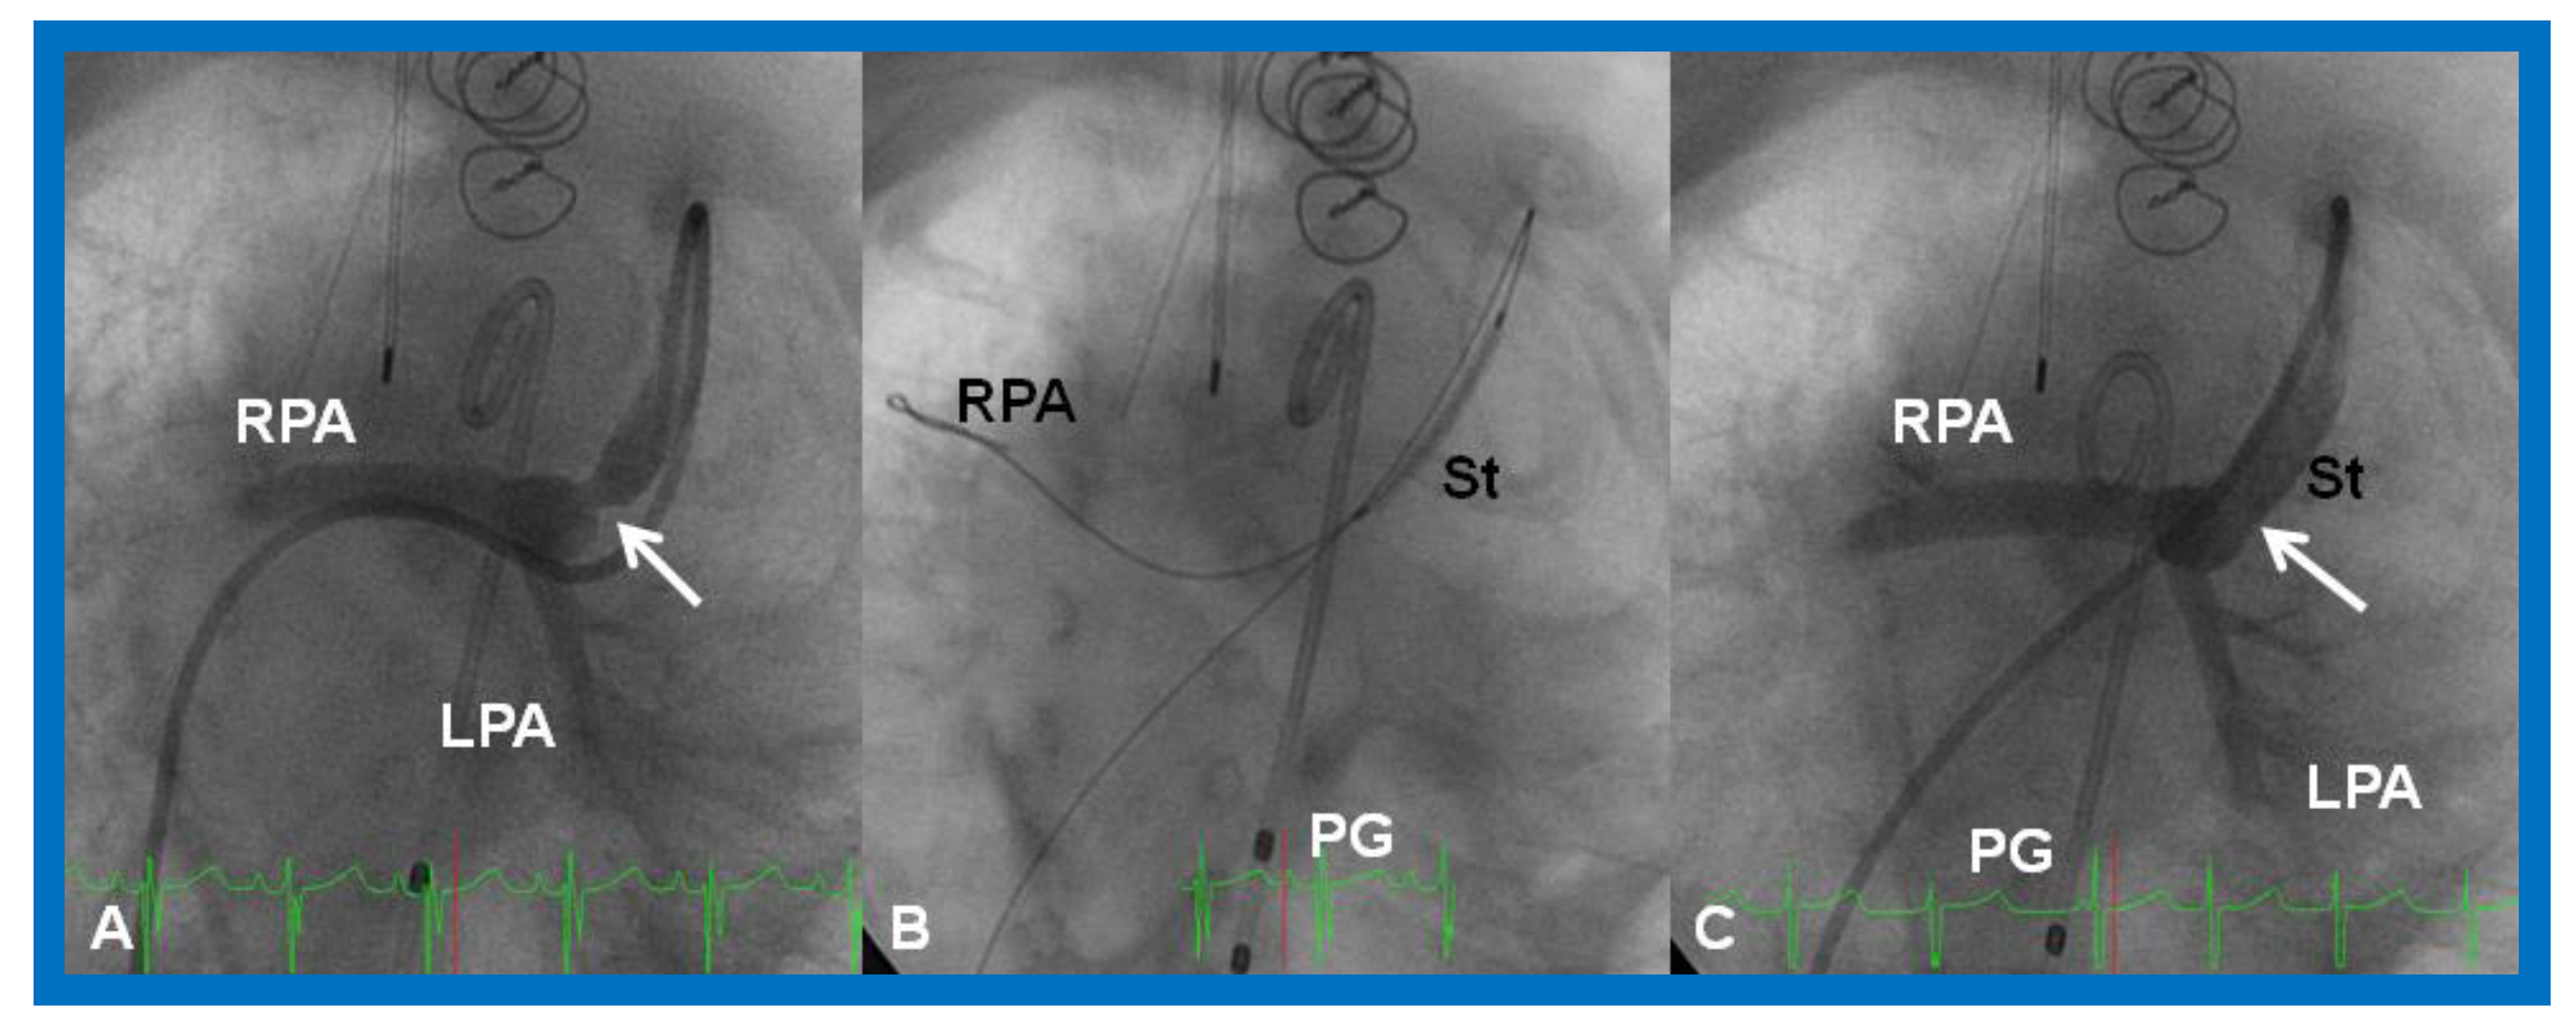

- Rao, P.S.; Balfour, I.C.; Singh, G.K.; Jureidini, S.B.; Chen, S. Bridge stents in the management of obstructive vascular lesions in children. Am. J. Cardiol. 2001, 88, 699–702. [Google Scholar] [CrossRef]

- Rao, P.S. Stents in the management of congenital heart disease in the pediatric and adult patients. Indian Heart J. 2001, 53, 714–730. [Google Scholar] [PubMed]

- Sahu, R.; Rao, P.S. Transcatheter stent therapy in children: An update. Pediatrics Ther. 2012, S5. [Google Scholar] [CrossRef]

- Tsounias, E.; Rao, P.S. Stent therapy for clotted Blalock-Taussig shunts. Congenit. Cardiol. Today 2010, 8, 1–9. [Google Scholar]